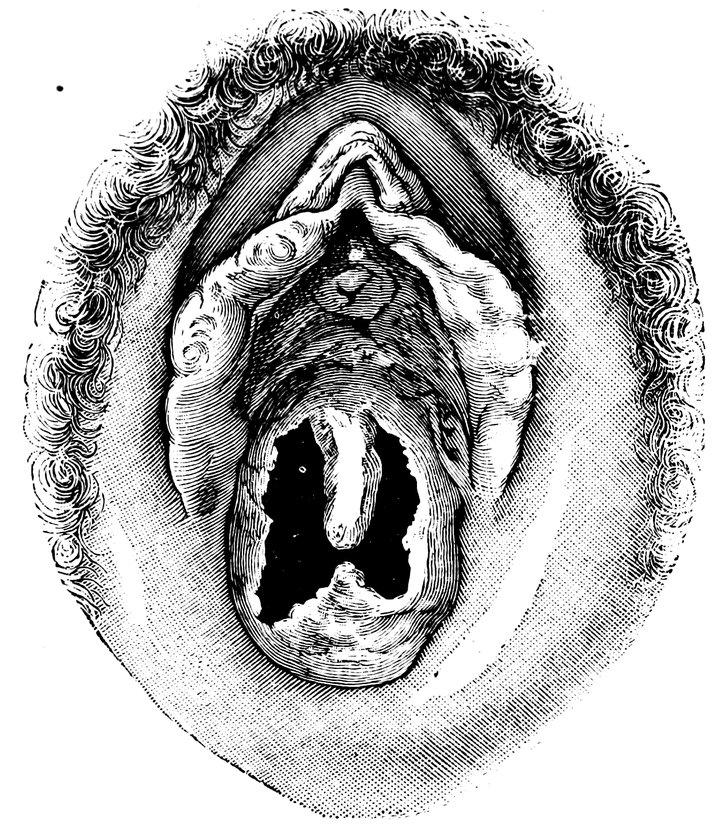

| 12. | Female external genital organs of a virgin | 54 |

| 13. | The external genital organs of a virgin | 55 |

| 18. | Annular Hymen | 64 |

| 19. | Annular Hymen | 64 |

| 20. | Semilunar Hymen | 65 |

| 21. | Annular Hymen with Congenital Symmetrical Indentations | 65 |

| 22. | Fimbriate Hymen | 65 |

| 23. | Deflorated Fimbriate Hymen | 65 |

| 24. | Septate Annular Hymen | 67 |

| 25. | Septate Semilunar Hymen | 67 |

| 26. | Extremely tough Annular Hymen with an obliquely disposed Septum | 67 |

| 27. | Septate Hymen with Apertures of unequal Size | 67 |

| 28. | Septate Hymen with Apertures of unequal Size | 68 |

| 29. | Hymen with rudimentary Septum | 68 |

| 30. | Hymen with posterior rudimentary Septum | 68 |

| 31. | Labiate Hymen with posterior rudimentary Septum | 68 |

| 32. | Hymen with anterior rudimentary Septum | 69 |

| 33. | Hymen with anterior rudimentary Septum projecting in a opiniform Manner | 69 |

| 34. | Hymen with anterior and posterior rudimentary Septa | 69 |

| 35. | Hymen with filiform Process projecting from the anterior Margin | 69 |

| 36. | Hymen in which there are two symmetrically disposed thinned Areas. The left of these is perforated | 69 |

| 37. | Very unusual form of Hymen | 70 |

| 38. | Semilunar Hymen with cicatrized Lacerations in its Border | 70 |

| 39. | Deflorated Semilunar Hymen with laterally disposed symmetrical Lacerations | 70 |

| 40. | Deflorated Annular Hymen with several cicatrized Lacerations | 70 |

| 41. | A. Septate Hymen in which defloration has been effected through one of the Apertures. U. Urethra. Cl. Clitoris. H. Cicatrized Margin. C. Septum. B. Lateral view of Septum | 70 |

| 42. | Deflorated Septate Hymen | 71 |

| x43. | Hymen with larger anterior and smaller posterior Apertures | 71 |

| 44. | Carunculæ Myrtiformes in a Primipara | 71 |

| 45. | Vaginal Inlet of a Multipara, without Carunculæ Myrtiformes. Slight Prolapse of Anterior and Posterior Vaginal Walls | 71 |